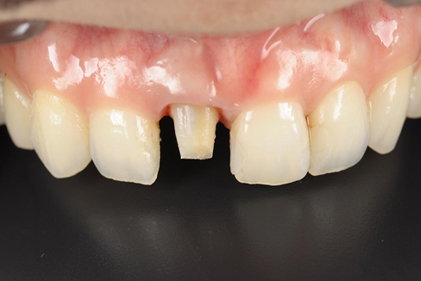

初診時

患者様の主訴は、「前歯の隙間が気になる」

でした。

矯正治療をおすすめしましたが、矯正治療の期間が長いということでセラミック治療を選択することになりました。写真をみるとすきっ歯も気になりますが、以前に詰めたプラスティックも変色して着色しており気になります。

仮歯

セラミックの前に仮歯を調整している段階になります。できればということで歯の長さも短くしたいというリクエストがありましたので、仮歯で調整をしながら様子を見ました。

歯の長さを短くする際に歯を削りますので神経の治療が必要になることがありますので、しみたり・噛んで痛くないか?を約1ヶ月様子を見ました。色・形など仮歯でほぼ問題ないということでしたので、最終的な型採りをしました。

セラミックセット

最終的なジルコニアボンドクラウンをセットしました。すきっ歯がまずなくなりました。また、長かった歯が短くなりましたので本人の希望に沿うことができました。